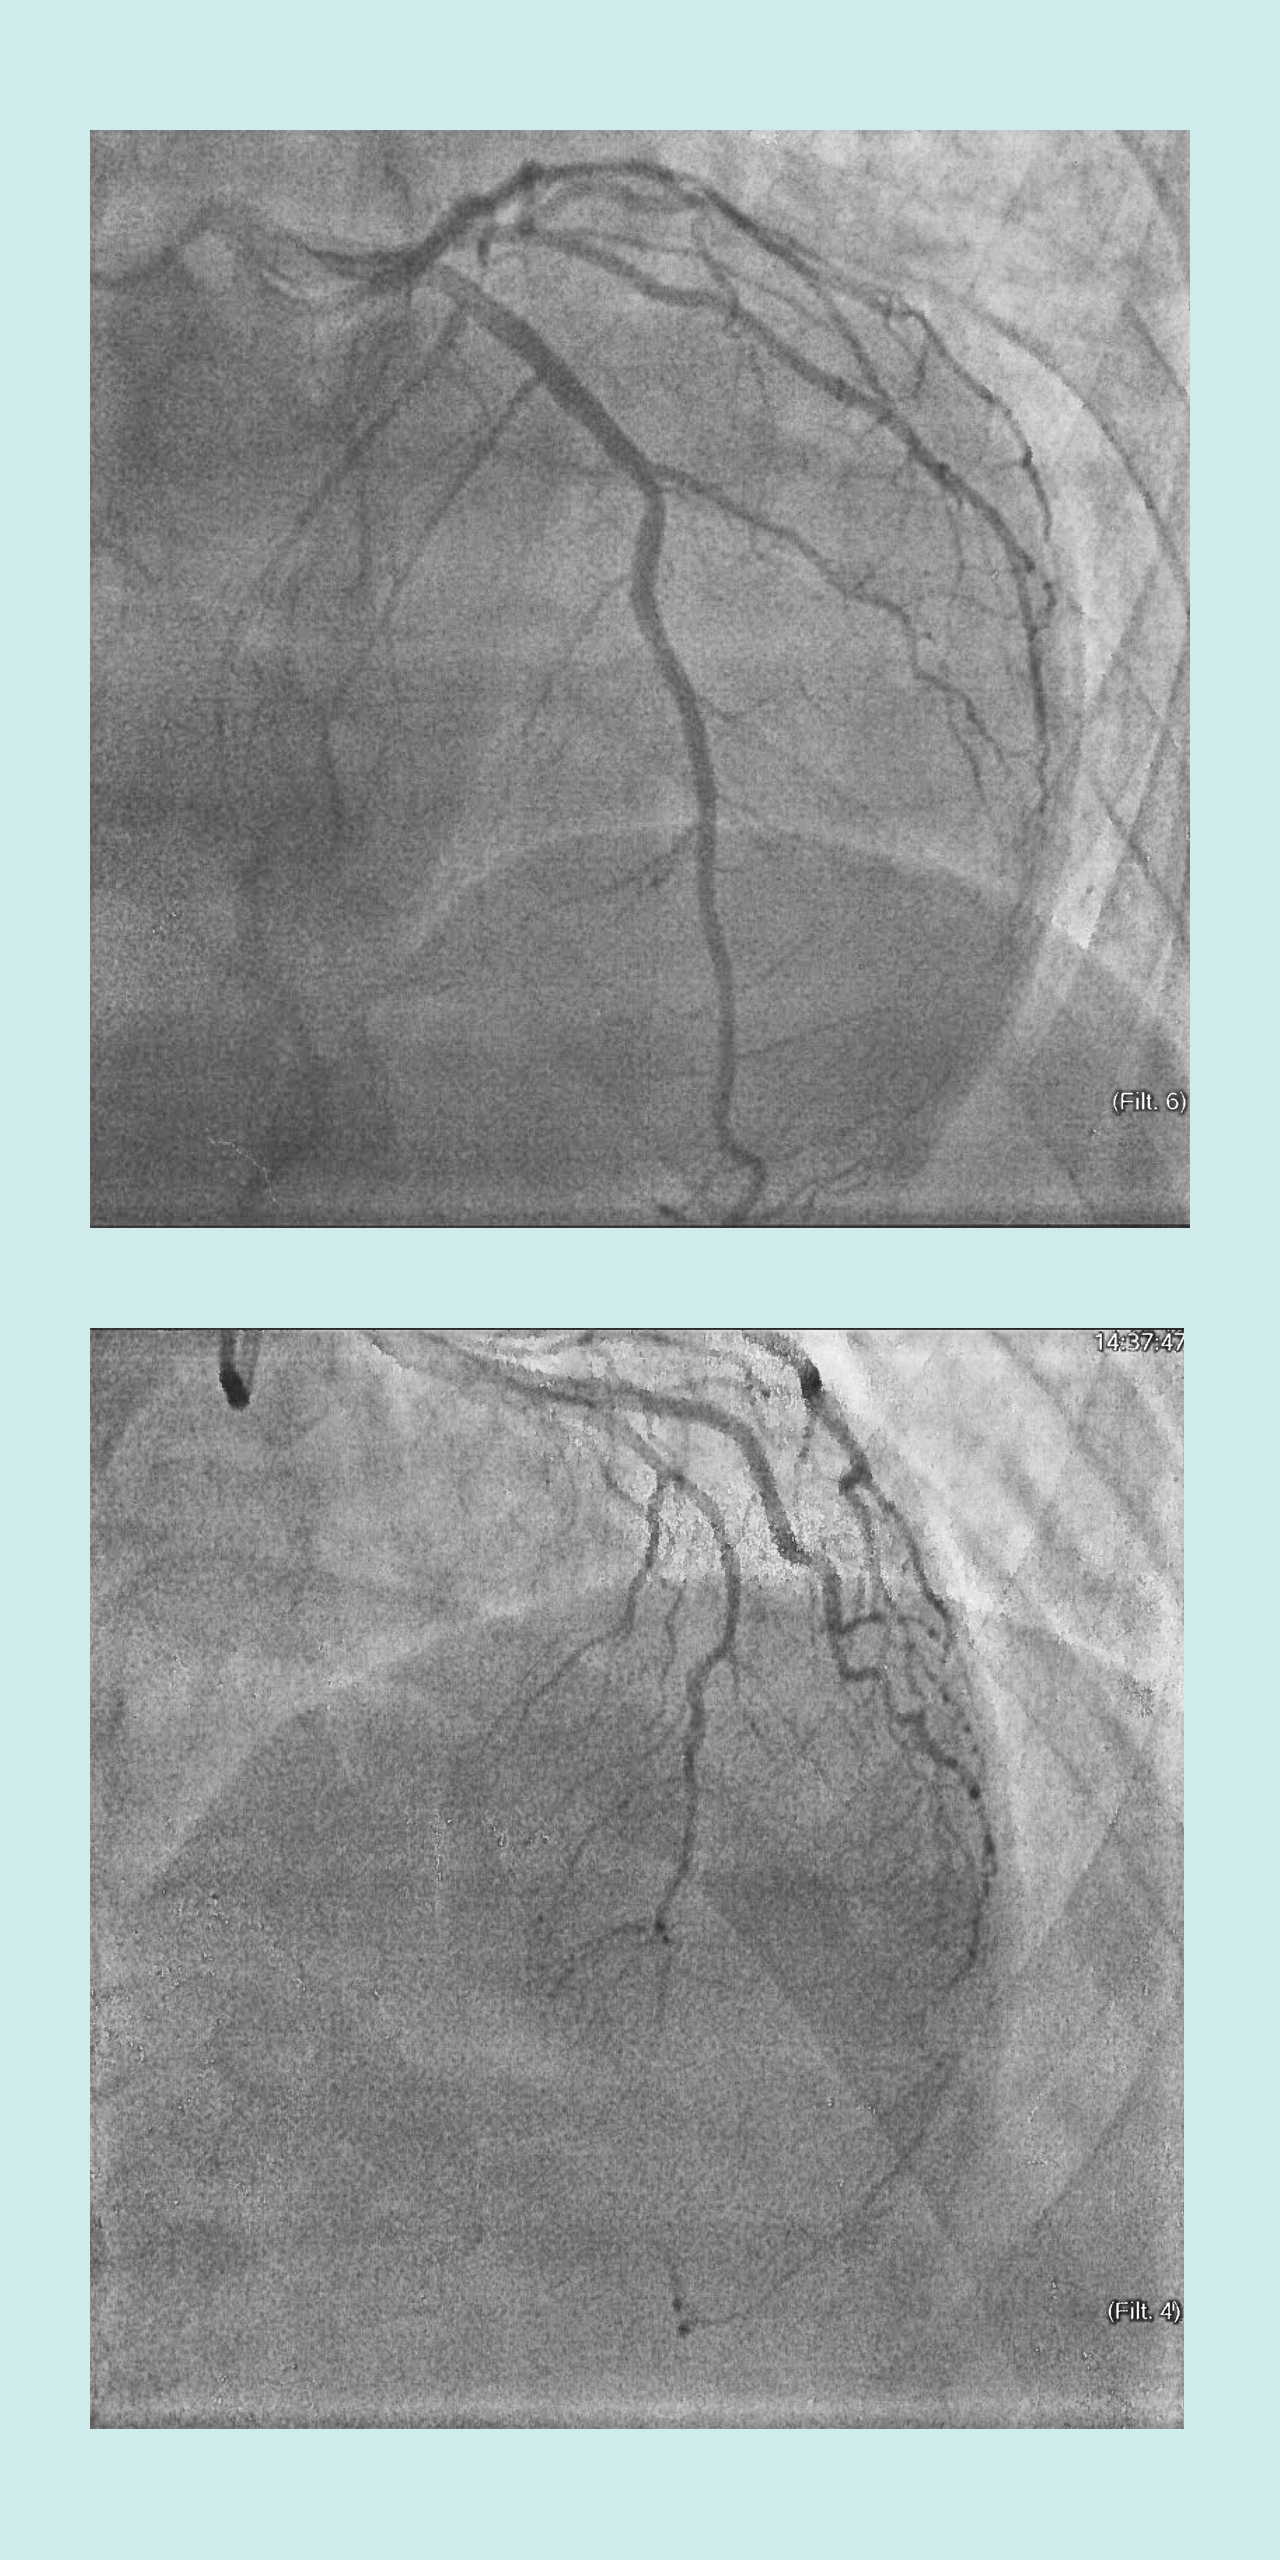

Cortesía de Jennifer Gaydosh Cuando el Dr. Wahl vio mis vasos sanguíneos durante la angiografía -en la que se inyecta un tinte en las arterias y se ve el flujo sanguíneo mediante rayos X- supo que tenía problemas. Llamó a dos de sus colegas y Heather se unió a ellos.

Al ver las imágenes de mi corazón enfermo, Heather preguntó: "¿Dónde está su DAI?" Se refería a la arteria descendente anterior de mi corazón, que suministraba sangre al ventrículo izquierdo, la bomba. Si se pierde ese flujo sanguíneo, es probable que se pierda la vida, por lo que se llama a la arteria descendente izquierda "la hacedora de viudas".

Uno de los médicos dijo: "Creo que se ha ido".

El diagnóstico era, de hecho, SCAD, exactamente lo que me había preocupado. Las fibras musculares de mi DAI se habían roto, bloqueando la arteria como una bandera aspirada sobre una toma de aire. Se había formado un coágulo y el flujo sanguíneo se había detenido. Yo también lo habría hecho, si no fuera porque mi brillante y fuerte corazón había empezado a formar una circulación colateral -vías alternativas a través de vasos sanguíneos más pequeños- para mantener vivo mi músculo cardíaco. Los atletas desarrollan la circulación colateral durante el estrés del ejercicio, o puede ocurrir espontáneamente durante un ataque al corazón. En cualquier caso, podría haberme salvado la vida.